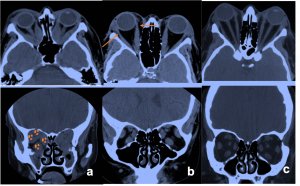

Most frequent involvement IR>MR>SR>LR. Superior Ophthalmic Vein may be enlarged due to apical compression | Axial and coronal section of non-contrast CT images of orbit showing three different patterns of TED. a) Bilateral fusiform enlargement of the extraocular muscles sparing the tendinous insertion with posterior crowding (orange stars) b) Bilateral fusiform enlargement of the extraocular muscles sparing the tendinous insertion along with increased orbital fat. c) Bilateral increased orbital fat (denoted by increase of hypodense areas of fat attenuation). EOM appears normal. |